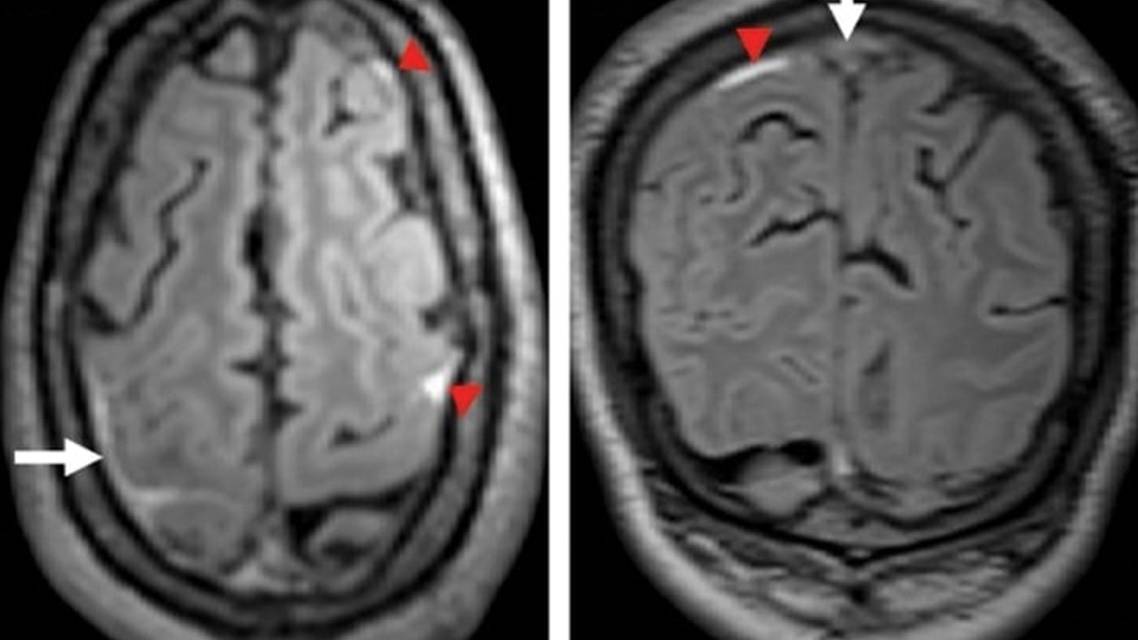

Cranial CT imaging revealed right frontal cortical SAH (Figure 1). Because there was no recent head trauma and the CT brain imaging showed convexal SAH, we proceeded with further imaging to evaluate the cause of nontraumatic SAH. MRI revealed right frontoparietal cortical SAH extending into the right central sulcus and thrombosis of multiple cortical veins (Figure 2A), superior sagittal sinus, and right vein of Trolard (Figure 2B). However, there were no signal abnormalities within the brain parenchyma. Magnetic resonance angiography (MRA) of the cerebral vessels had unremarkable results (Figure 3). Magnetic resonance venography (MRV) revealed thrombosis of the superior sagittal sinus (Figure 4).

Individuals with CVT may experience focal neurologic deficits or seizures due to edema, hemorrhage, or venous infarction within the brain parenchyma. In our case, brain MRI did not show any obvious abnormalities in the brain parenchyma. However, the presence of cortical SAH in the right central sulcus could account for the transient left-sided sensorimotor focal neurologic deficits. The mechanism of TIA-like episodes in individuals with CVT is a topic of debate. Some previous studies have suggested that theories such as cortical spreading depression or reduced regional cerebral perfusion could explain the occurrence of TIA-like episodes in individuals with cortical venous thrombosis.7,21